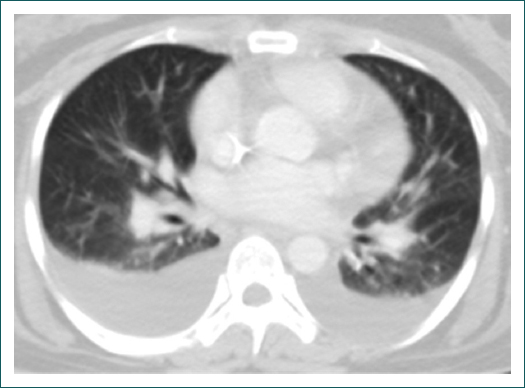

Clínicamente, la paciente presentaba mialgias, artralgias y disnea de mínimos esfuerzos, uso de musculatura accesoria de la respiración, estertores crepitantes infraescapulares en el hemitórax derecho, derrame pleural derecho, hepatoesplenomegalia, artritis en las articulaciones metacarpofalángicas e interfalángicas proximales, metatarsofalángicas, carpo, rodillas y tobillos. La tomografía de tórax mostró derrame pleural bilateral con afectación intersticial y ocupación alveolar a nivel basal bilateral compatible con neumonía basal bilateral y actividad inflamatoria intersticial (Fig. 2). Se inició manejo con factor estimulante de colonias de granulocitos y monocitos, y con piperacilina-tazobactam. Se solicitó panel para virus herpes simple tipos 1 y 2, virus de Epstein Barr, citomegalovirus, y serología para virus de las hepatitis B y C, y para el VIH, que fueron negativos. Cultivo de expectoración, hemocultivo y urocultivo sin desarrollo. Factor reumatoide 15.6 UI/ml, haptoglobina 337 mg/dl (35-250 mg/dl), anticoagulante lúpico 1.2-1.5 débilmente positivo; anticardiolipinas elevadas: IgG 45.9 GLP/ml (< 20 GLP/ml), IgM 120 MPL/ml (< 20 MLP/ml); anticuerpos anti-beta(2)-glucoproteína I normales: IgG 14.4 GPL/ml (< 20 GLP/ml) e IgM 9.2 MPL/ml (< 20 MLP/ml); sin antecedente de trombosis.